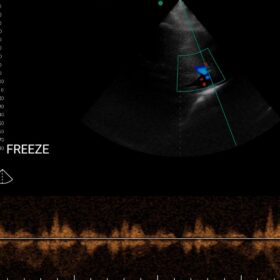

Cardio 2D, Color and PW doppler